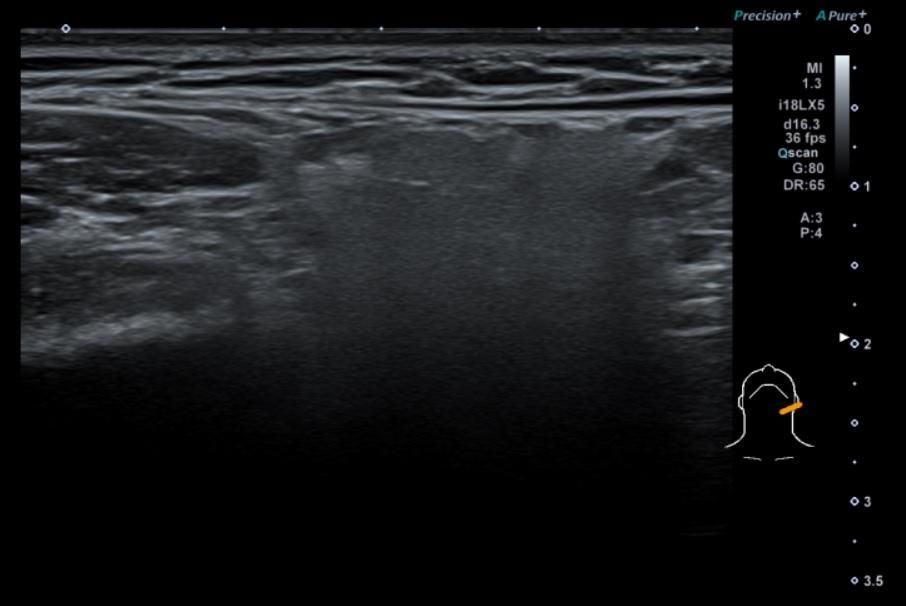

• 3번 째 사진